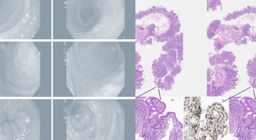

Лекарство от давления вызвало энтеропатию и диарею у пожилой итальянки

Итальянские врачи описали случай тяжелого поражения кишечника у пожилой пациентки, которая на протяжении года принимала олмесартан.N + 1